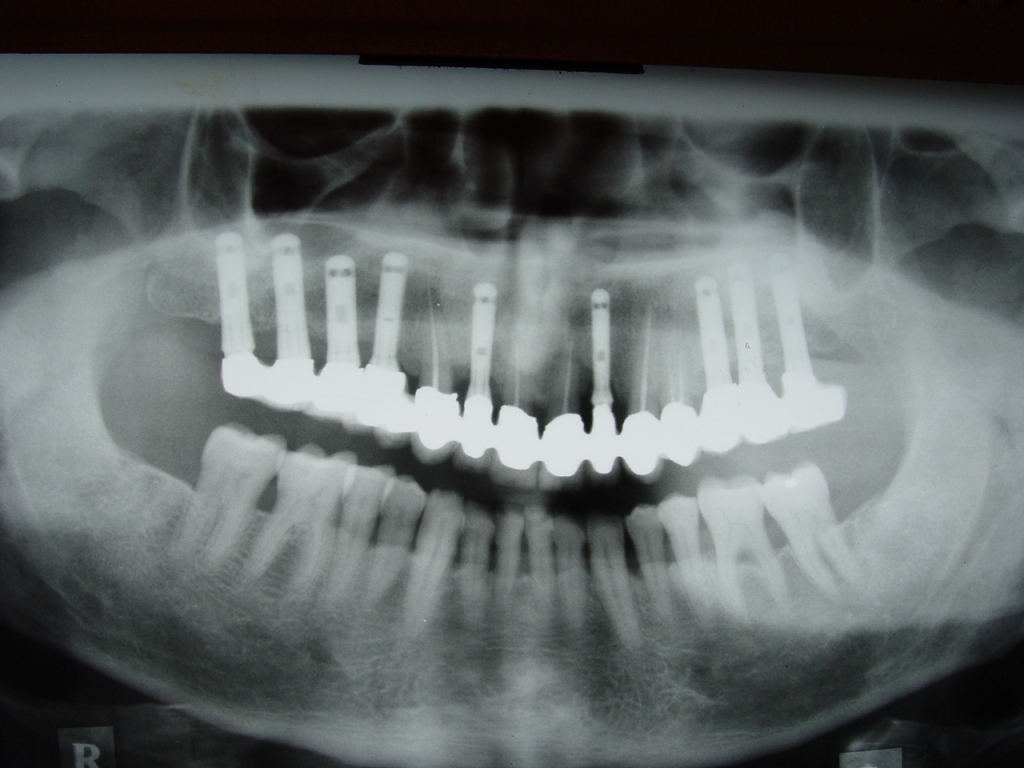

שתל בצילום רנטגן – תמיכת עצם מלאה

השתלים ברפואת שיניים מחליפים את שורש השן החסרה.השתלים עשויים מחומרים התואמים את רקמות הגוף, וזאת על-מנת שלא יידחו. השתלים הדנטליים משמשים כתמיכה לשיניים דמויות השיניים הטבעיות כדי לאפשר למטופל מחוסר השיניים לחייך, לדבר בביטחון וללעוס מזון.

צילום פנורמי עם שתלים